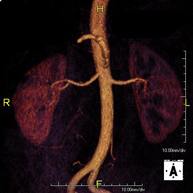

Prova diagnòstica no invasiva que consisteix en l'obtenció d'imatges d'alta definició anatòmica de tot el cos mitjançant l'ús d'un camp electromagnètic i ones de ràdio (amb un emissor i un receptor). No utilitza radiació ionitzant. És una prova molt important en la recerca de metàstasi en pacients amb neoplàsia coneguda. No requereix preparació prèvia. No és necessari l'ús de contrast paramagnètic (Gadolini). - Angio RM d'Aorta-ilíaca

Prova diagnòstica no invasiva que consisteix en l'estudi de l'artèria aorta abdominal i de les artèries ilíaques, amb l'obtenció d'imatges d'alta definició anatòmica mitjançant l'ús d'un camp electromagnètic i ones de ràdio (amb un emissor i un receptor). És indispensable l'ús de contrast paramagnètic (Gadolini). No utilitza radiació ionitzant. La qualitat de les imatges permet realitzar reconstruccions en 2D i 3D. Aquesta prova està especialment indicada com a estudi prequirúrgic (mapa vascular) abans d'intervencions percutànies o quirúrgiques d'aorta abdominal i artèries ilíaques, per a l'estudi complementari en pacients amb isquèmia de membres inferiors, etc. - Angio RM Arterial d'extremitats inferiors